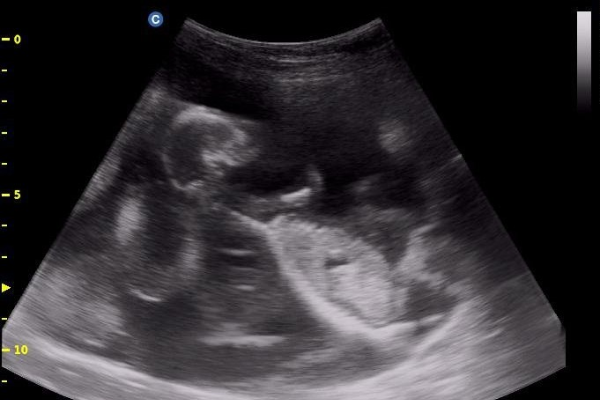

Application of ultrasound technology in the reproductive management of small ruminants